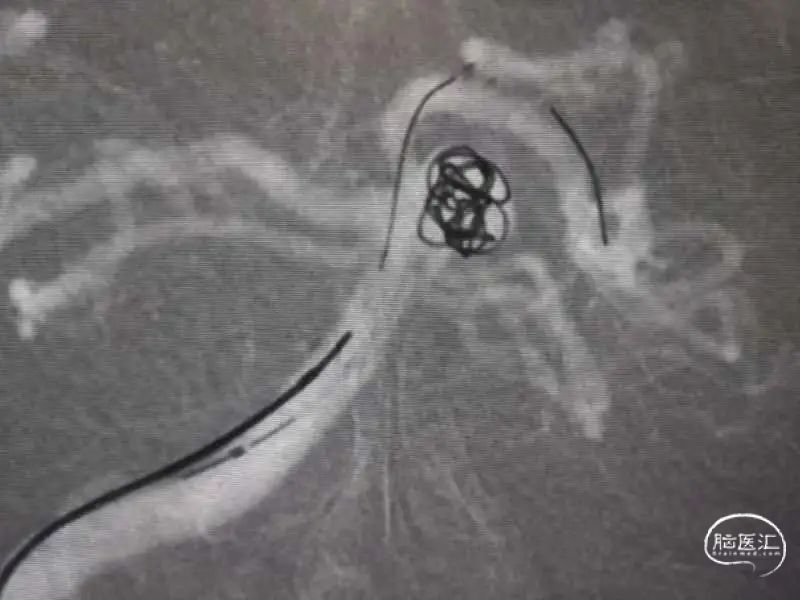

先用6-15瘤内成篮,可见部分弹簧圈袢突入基底动脉。

将Enterprise 4.5-22支架输送到位后安全释放,支架覆盖动脉瘤颈,远端锚定在左侧大脑后动脉P1段,近端释放在基底动脉。

依次填入5-15、3-8、2-8、2-6的弹簧圈。

撤除微导管后造影,提示动脉瘤栓塞满意,基底动脉、双侧大脑后动脉、小脑上动脉血流通畅。